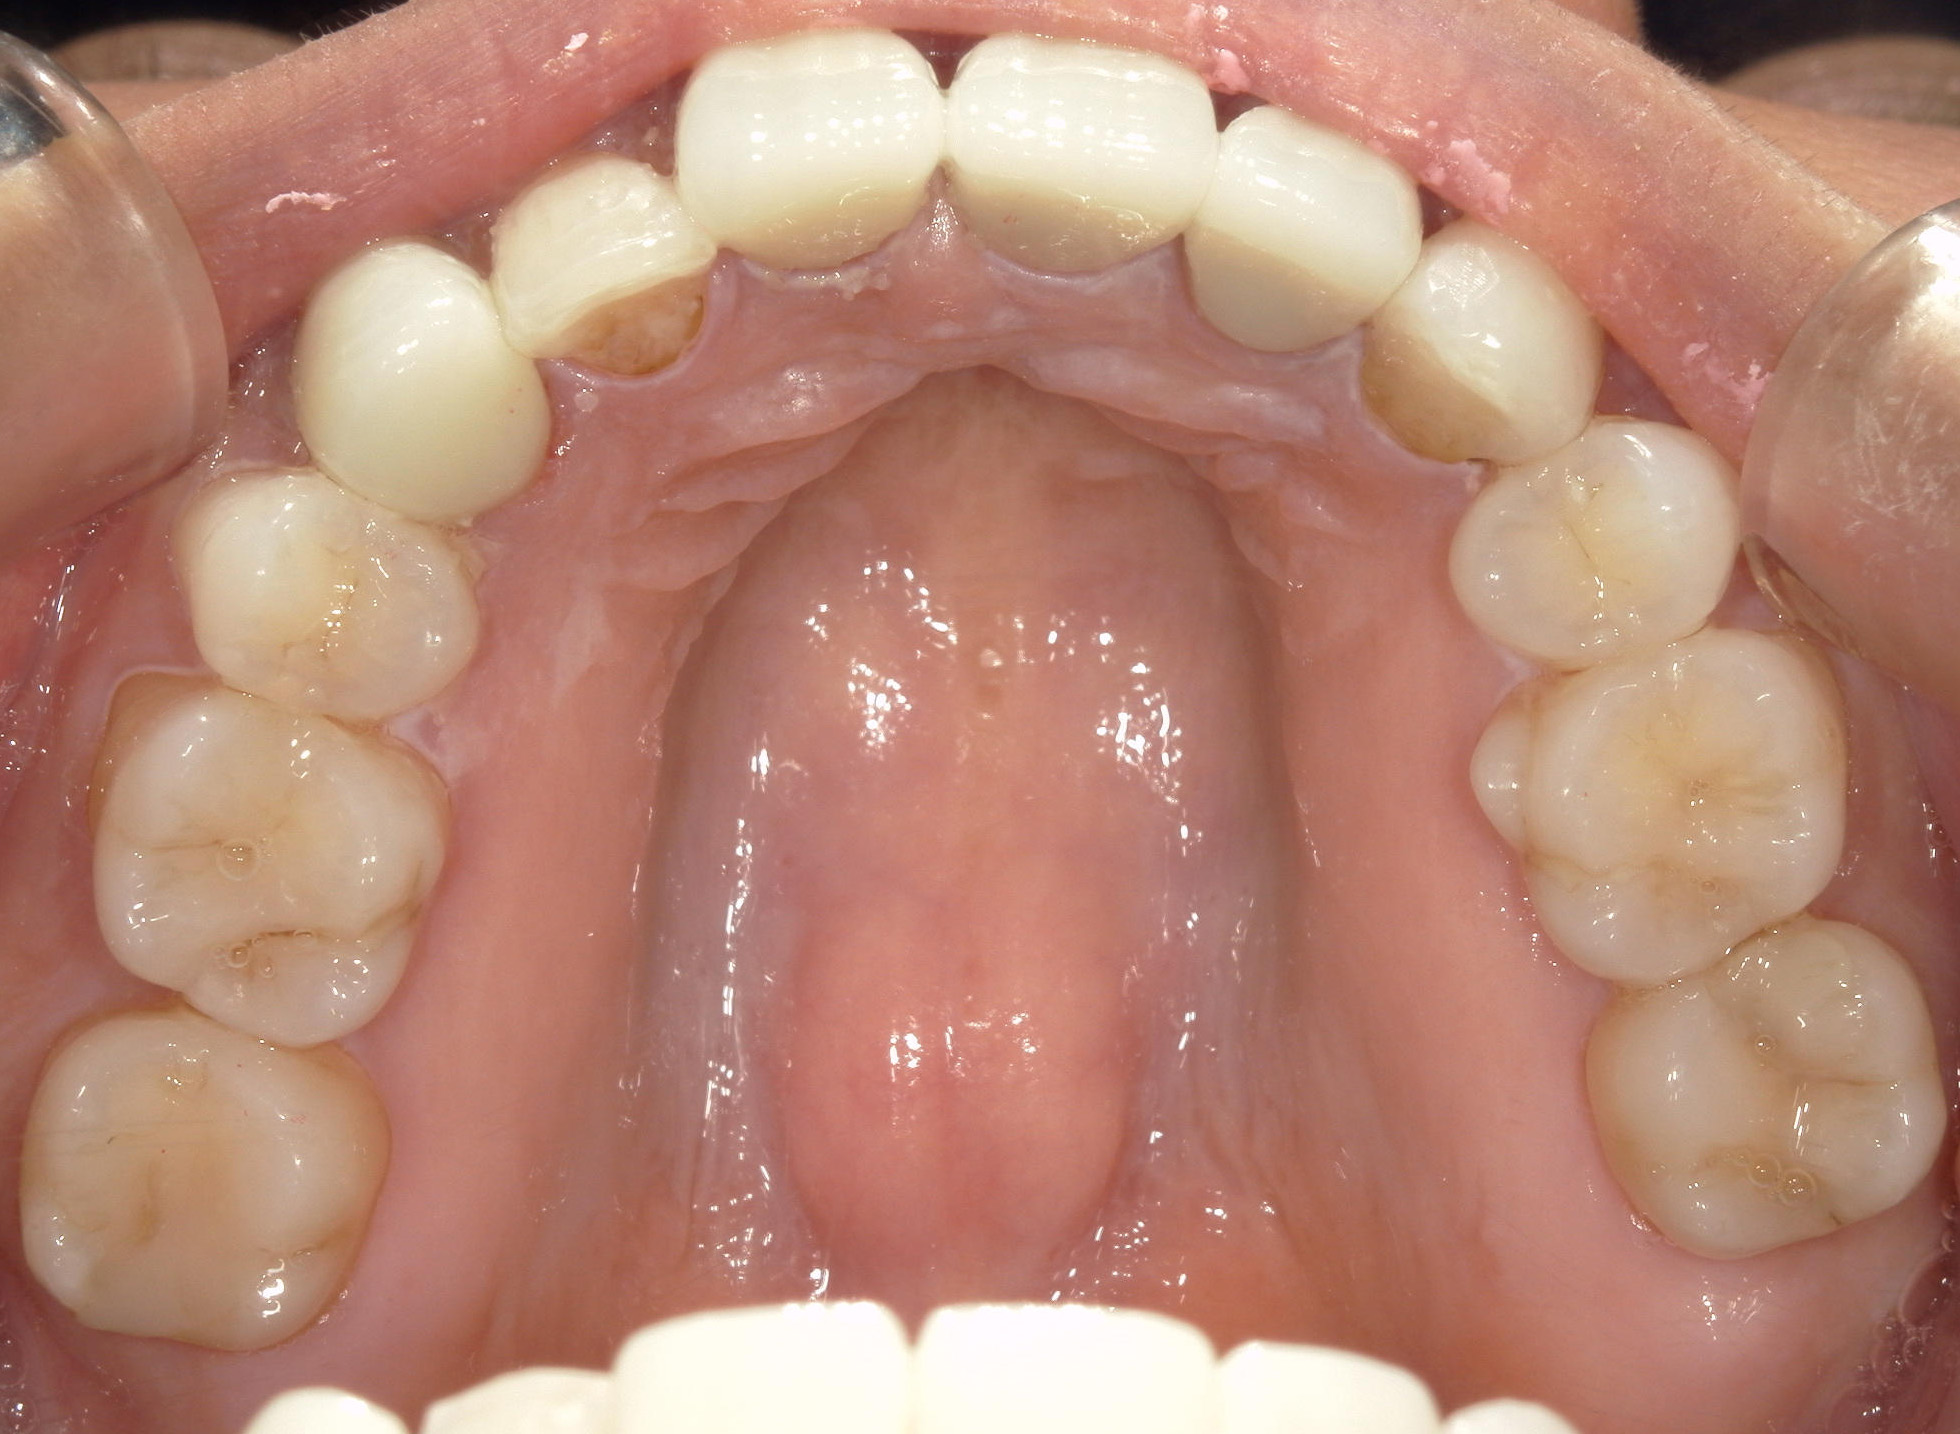

全顎ワイヤー矯正 症例(82)

主訴: 前歯の歯並びが気になる。

上下左右 第一小臼歯(4本)、左右上 親不知(2本)を抜歯。

ミニインプラント、アップライトスプリングを併用。

矯正前に左右上前歯4本を仮歯に変え、矯正治療後にセラミック(SHT)に冠せなおしました。

カテゴリー : ガタガタ(叢生)